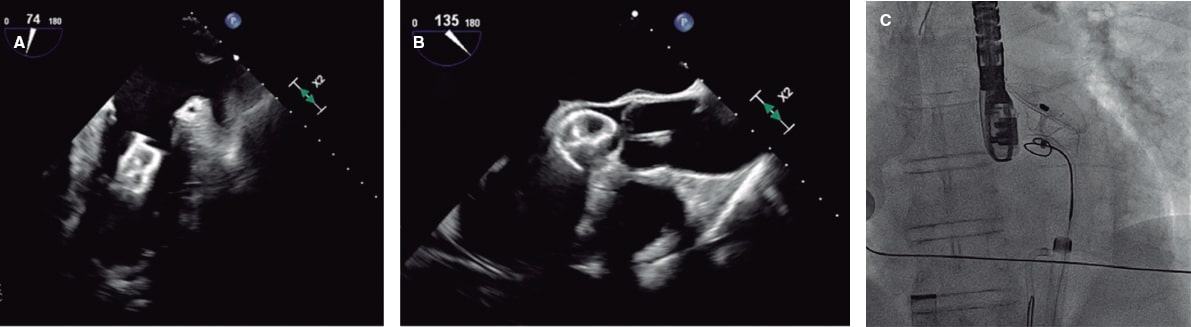

Figure 5 and figure 6 illustrate examples of left atrial appendage device embolization.

Figure 5. Intraoperative transesophageal echocardiography (TEE) and fluoroscopy of left atrial appendage closure with a 25-mm Amulet device. A: the device migrated to the left ventricle (LV). B: an 8-Fr JR4 guiding catheter with a 20-mm snare was introduced via left femoral access, capturing the device by the distal lobe screw and allowing it to be pulled into the descending aorta. C: afterwards, the right femoral artery was cannulated with a 16-Fr introducer sheath; using a guiding catheter and a 30-mm snare, the device was again captured by the distal lobe screw, pulled back, and finally extracted.